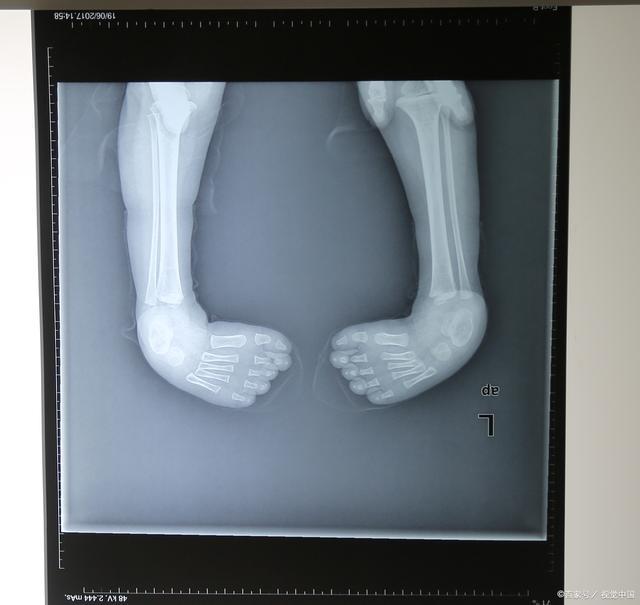

马蹄内翻足可以是单侧肢体受累,也可以是双侧均为马蹄内翻足。如下图所示,为一例双侧马蹄内翻足宝宝。

双侧马蹄内翻足宝宝